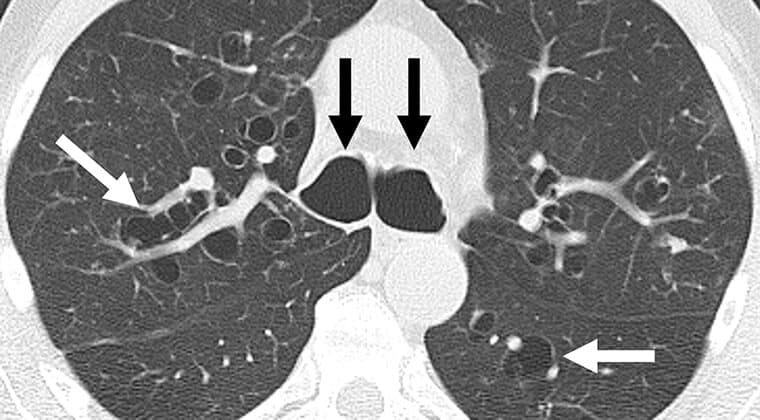

Bronquiectasias

Las bronquiectasias son una dilatación irreversible de los bronquios debido a infecciones recurrentes o inflamación crónica. En México, afecta al 12 % de pacientes con EPOC avanzado (INER, 2023) y es frecuente en personas con historial de tuberculosis mal tratada.